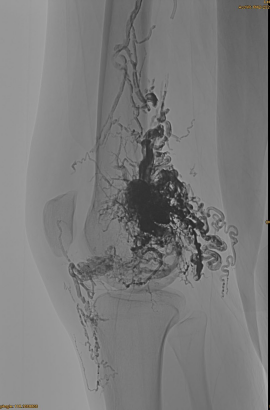

DSA اولیه:

نتیجه نهایی:

به سختی هرگونه خروج وریدی:

مرحله دیررس ، یک EMBO دیگر لازم است ، اما خیلی بهتر: